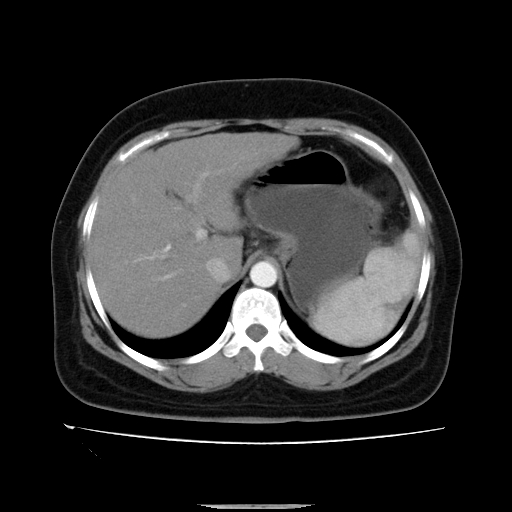

标题: CT14225:女性46岁。当地B超示肝内占位,来我院作CT检查。请 [打印本页]

标题: CT14225:女性46岁。当地B超示肝内占位,来我院作CT检查。请

速升速降,支持肝癌.脾体积增大,形态欠规整,请询问病史是否做过脾动脉栓塞.

速升速降,支持肝癌可能。

快进快出,符合肝癌表现-----------

肝内结节强化特点符合原发性肝癌表现,脾脏改变考虑为增大及先天发育所致。

动脉期病原灶明显强化高于肝密度且中央有无强化区,静脉期强化程度下降明显,延迟低于肝密度,考虑肝腺瘤可能性大,

此患者虽然符合快进的特点,却不符合快出的特点,因为门脉期几乎是等密度,不符合肝癌的增强表现,所以我考虑肝局灶性结节增生可能性大